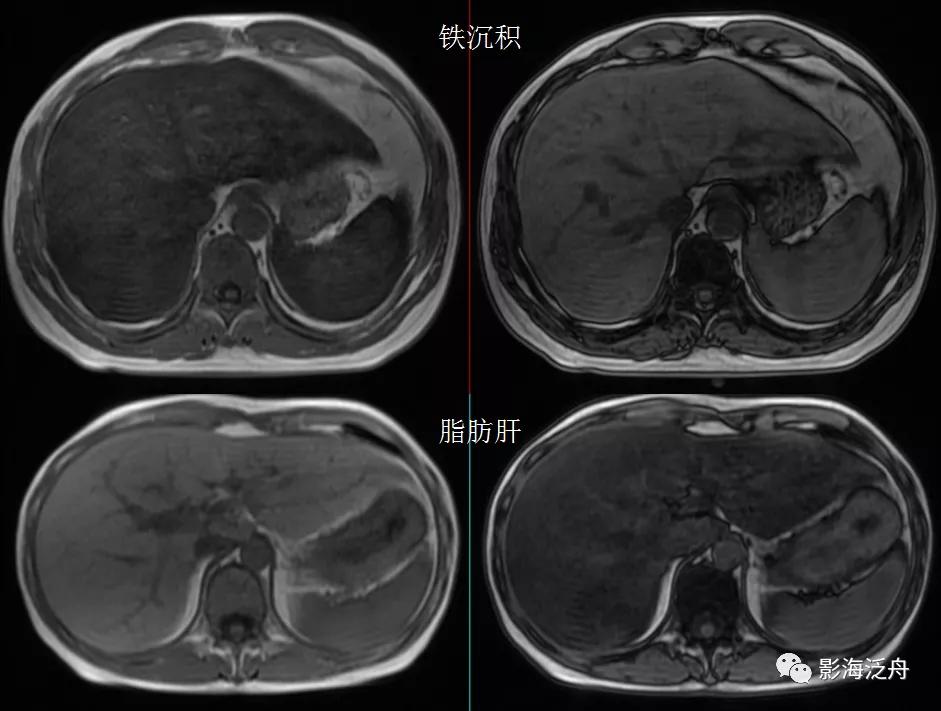

将铁沉积与脂肪肝的同反相位T1WI图像放在一起对比观察,可以看出两者的信号变化正好相反。

同一患者的T2WI抑脂序列图像,肝实质信号显著减低(红箭),同层面脾实质信号亦明显减低(黄箭),注意椎体及附件的信号也有明显减低(绿箭)。

将该患者与正常人的T2WI抑脂图像放在一起对比观察,用以加深印象。注意观察肝实质、脾实质、椎体及附件的信号变化。